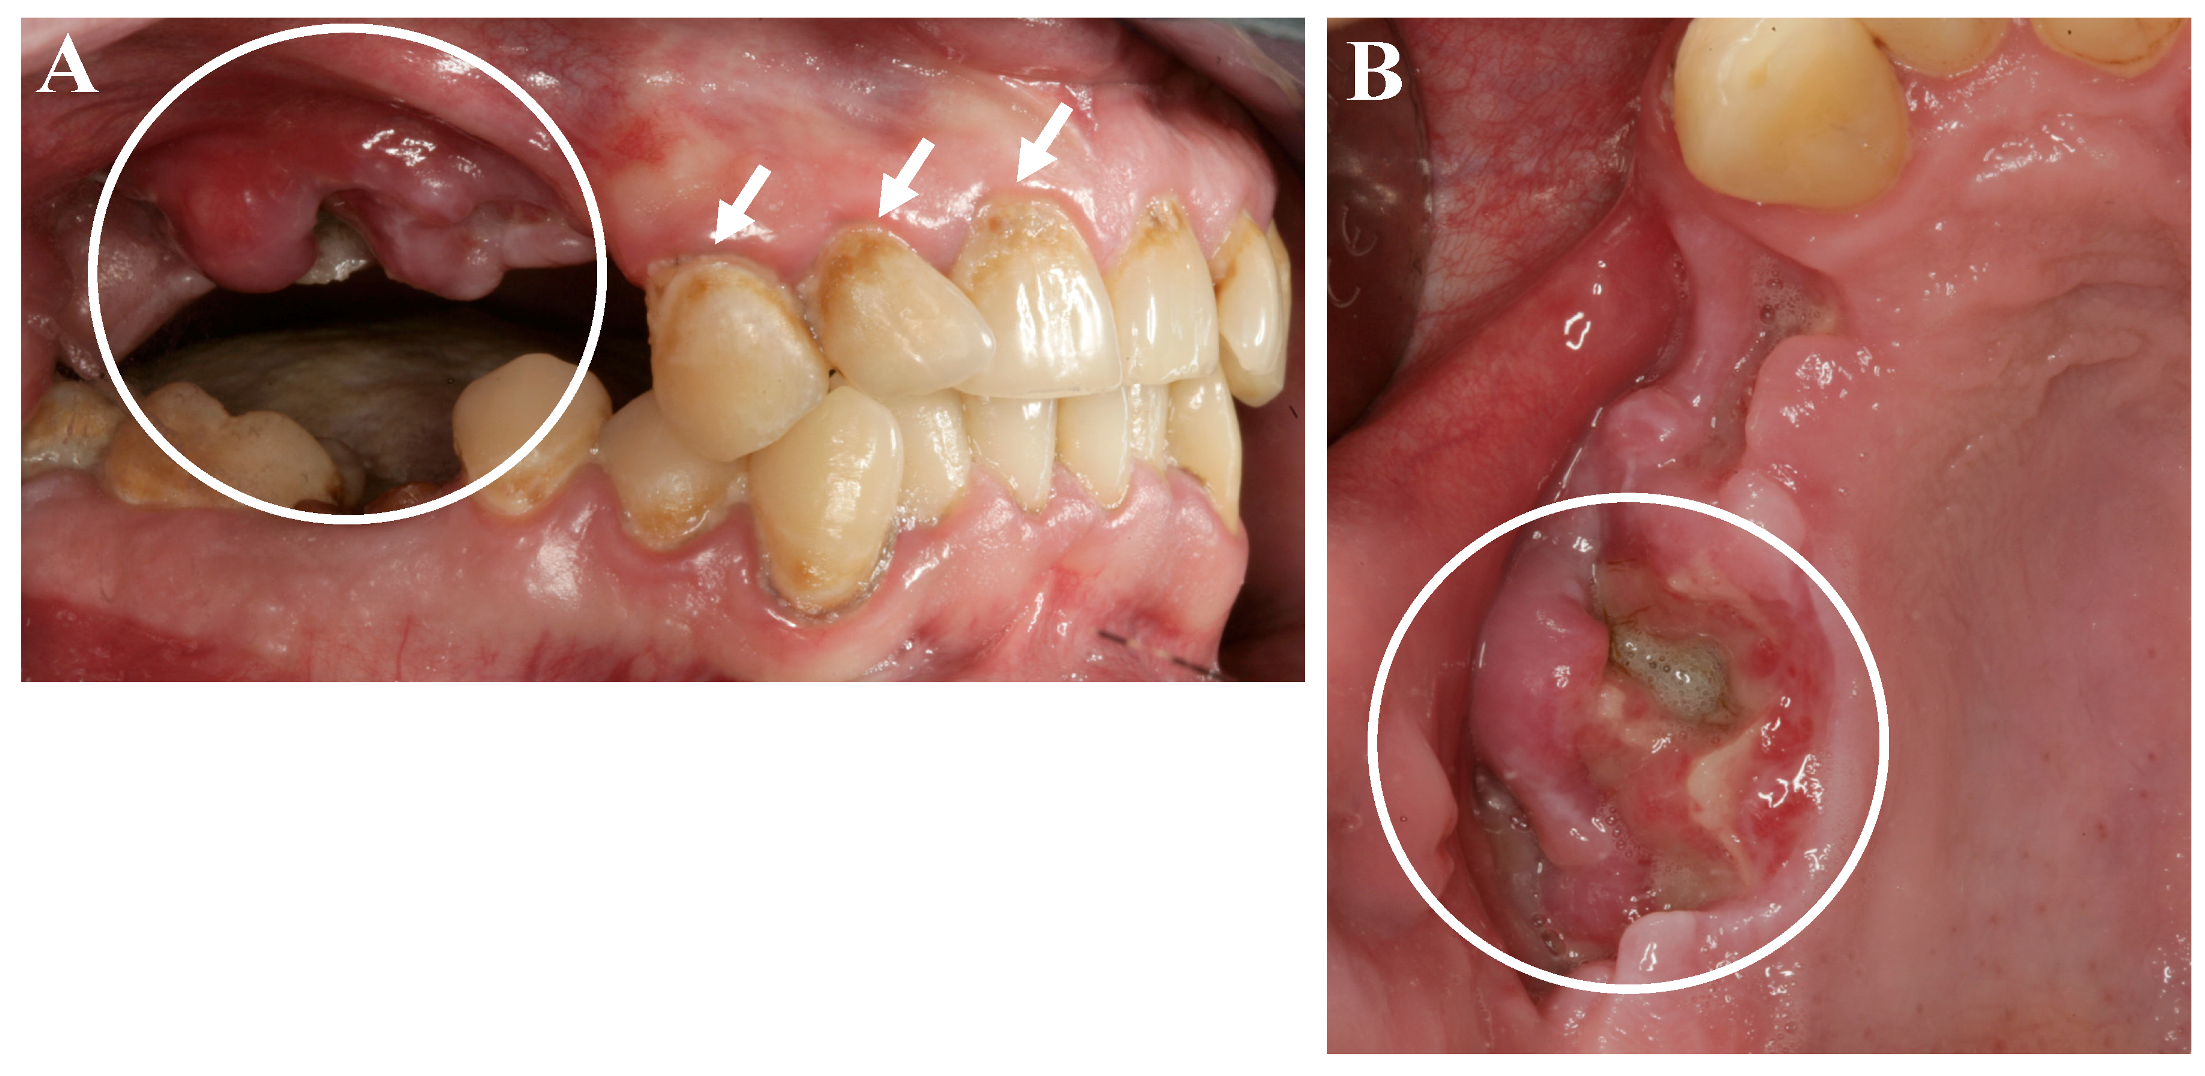

As a further side effect, a condition known as “meth mouth” has been increasingly reported and is characterized by xerostomia, extensive carious lesions, enamel erosions, extensive teeth crunching, bruxism, muscle trismus, and lockjaw [1,2,6], see Figure 1 and Figure 2.

Figure 1.

Oral and dental situation of a young patient after long years of methamphetamine abuse. (A) Characteristic cervical carious lesions (white arrows) and a severe wound healing disturbance with exposed jaw bone and a superinfection of the surrounding tissues of the maxilla (white circle), two weeks after tooth extraction alio loco; (B) View on the exposed bone of the maxilla (white circle) [9].

In recent years, case reports and studies on osteonecrosis after long-term methamphetamine abuse similar to the medication-related osteonecrosis of the jaws (MRONJ) have been published. Basin et al., reported cases of jaw necrosis in patients after desomorphin abuse in Russia, which has been confirmed by further studies [5,6,7,8]. Recently, Pabst and Werkmeister presented a case report of a young patient (male, 26 years) after four years of “meth” abuse and the development of an extended ONJ in the maxilla after tooth extractions, see Figure 1 and Figure 2 [9]. The patient had no further general diseases or allergies. His patient history was unobtrusive with exception of the “meth” abuse. A surgical wound revision of the affected areas was performed with general anesthesia, including a resection of necrotic bone and a saliva-proof wound closure under antibiotic treatment. The sutures were removed on day 21 postoperatively. To date, regular intraoral soft-tissue conditions can be observed. Further, restorative dentistry has been performed in private practice to restore the remaining teeth [9].